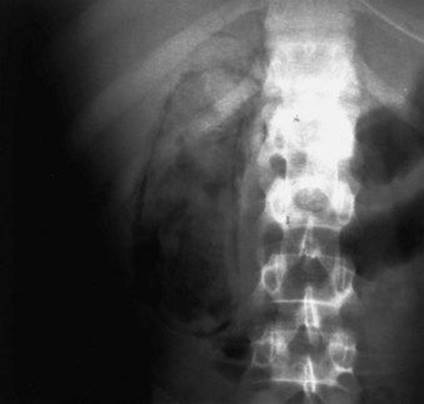

38 The pertinent area of a plain x-ray film of the abdomen of a 78-year-old diabetic man with right upper quadrant pain is shown below. Which of the following is the appropriate next step?

A Ultrasound imaging of the gallbladder

image

Ref.: 2, 3

Comments

Emphysematous cholecystitis occurs most typically in elderly diabetic men. Curvilinear radiolucencies in the right upper quadrant have the configuration of the gallbladder, are in the location of the gallbladder, and are diagnostic of gas in the gallbladder wall. In their totality, they are pathognomonic of emphysematous cholecystitis. Gas may also be seen in the gallbladder lumen. This condition is associated with a high incidence of gallbladder necrosis, perforation, and sepsis. Unnecessary diagnostic examinations would only delay prompt surgical therapy and possibly affect the outcome adversely. Urgent surgery is needed. An ultrasound study of an emphysematous gallbladder would show highly reflective shadows as a result of the gas. Differentiation from bowel gas may be difficult, although the diagnosis is usually evident. About one third of patients do not have stones. CT would show the abnormal gas in the gallbladder wall, lumen, or both. HIDA scans would fail to allow visualization of the gallbladder. ERCP is unnecessary.